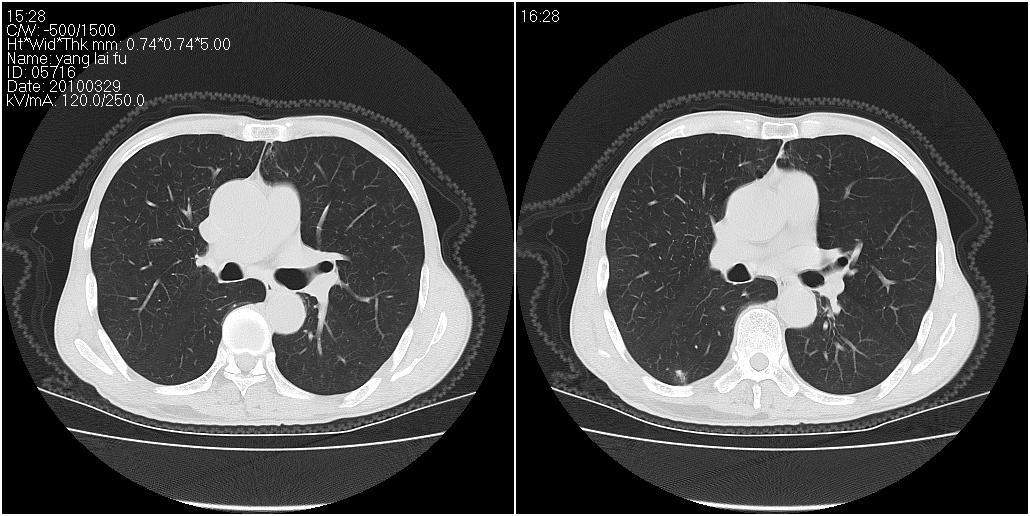

右肺中叶阻塞性不张及肺炎,高度怀疑支气管占位,建议纤支镜检查!

考虑右肺中叶感染。左肺下叶支扩。

右中肺阻塞性炎症,建议纤支镜!双下支扩感染。

1)右肺中叶慢性炎症并支气管扩张,节段性肺不张。2)两肺下叶支气管扩张。

1)右肺中叶慢性炎症并支气管扩张,节段性肺不张。2)左肺下叶支气管扩张